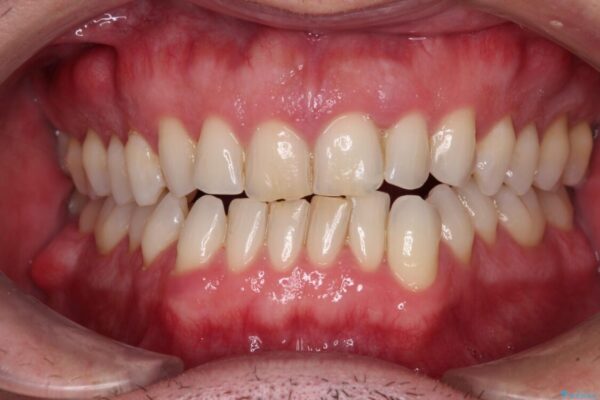

治療後

• 前歯でものを噛みきりたい 目立たない装置でのワイヤー矯正 治療後画像

治療後について

舌のトレーニング自体は簡単なものですが、無意識下でも舌が突出しないようにしなければならないため、毎日継続することが最大の難関です。

時間はかかりましたがトレーニングを頑張ってくださり、無事に前歯を接触させることができました。